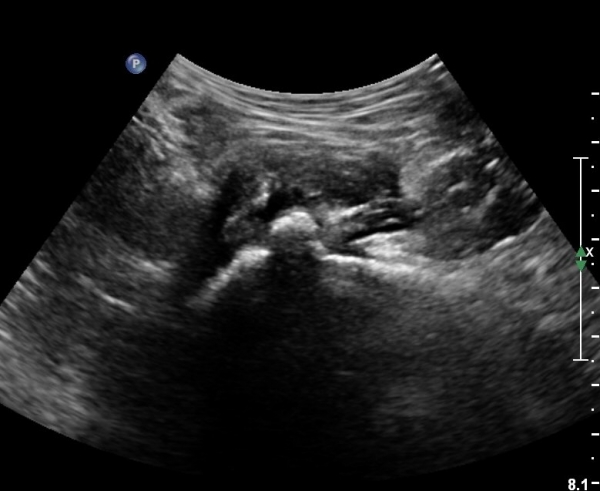

[¾ûµ¢ÀÌ] ¾ûµ¢ÀÌ °üÀý¼ø ÆÄ¿­ÀÇ ÃÊÀ½ÆÄ°Ë»ç(ultrasonography of labrum tear of hip joint)

Sonography of the Acetabular Labrum Visualization of Labral Injuries During Intra-Articular Injections

What is the role of clinical tests and ultrasound in acetabular labral tear diagnostics?

Sonographic evaluation of anterosuperior hip labral tears with magnetic resonance arthrographic and surgical correlation.